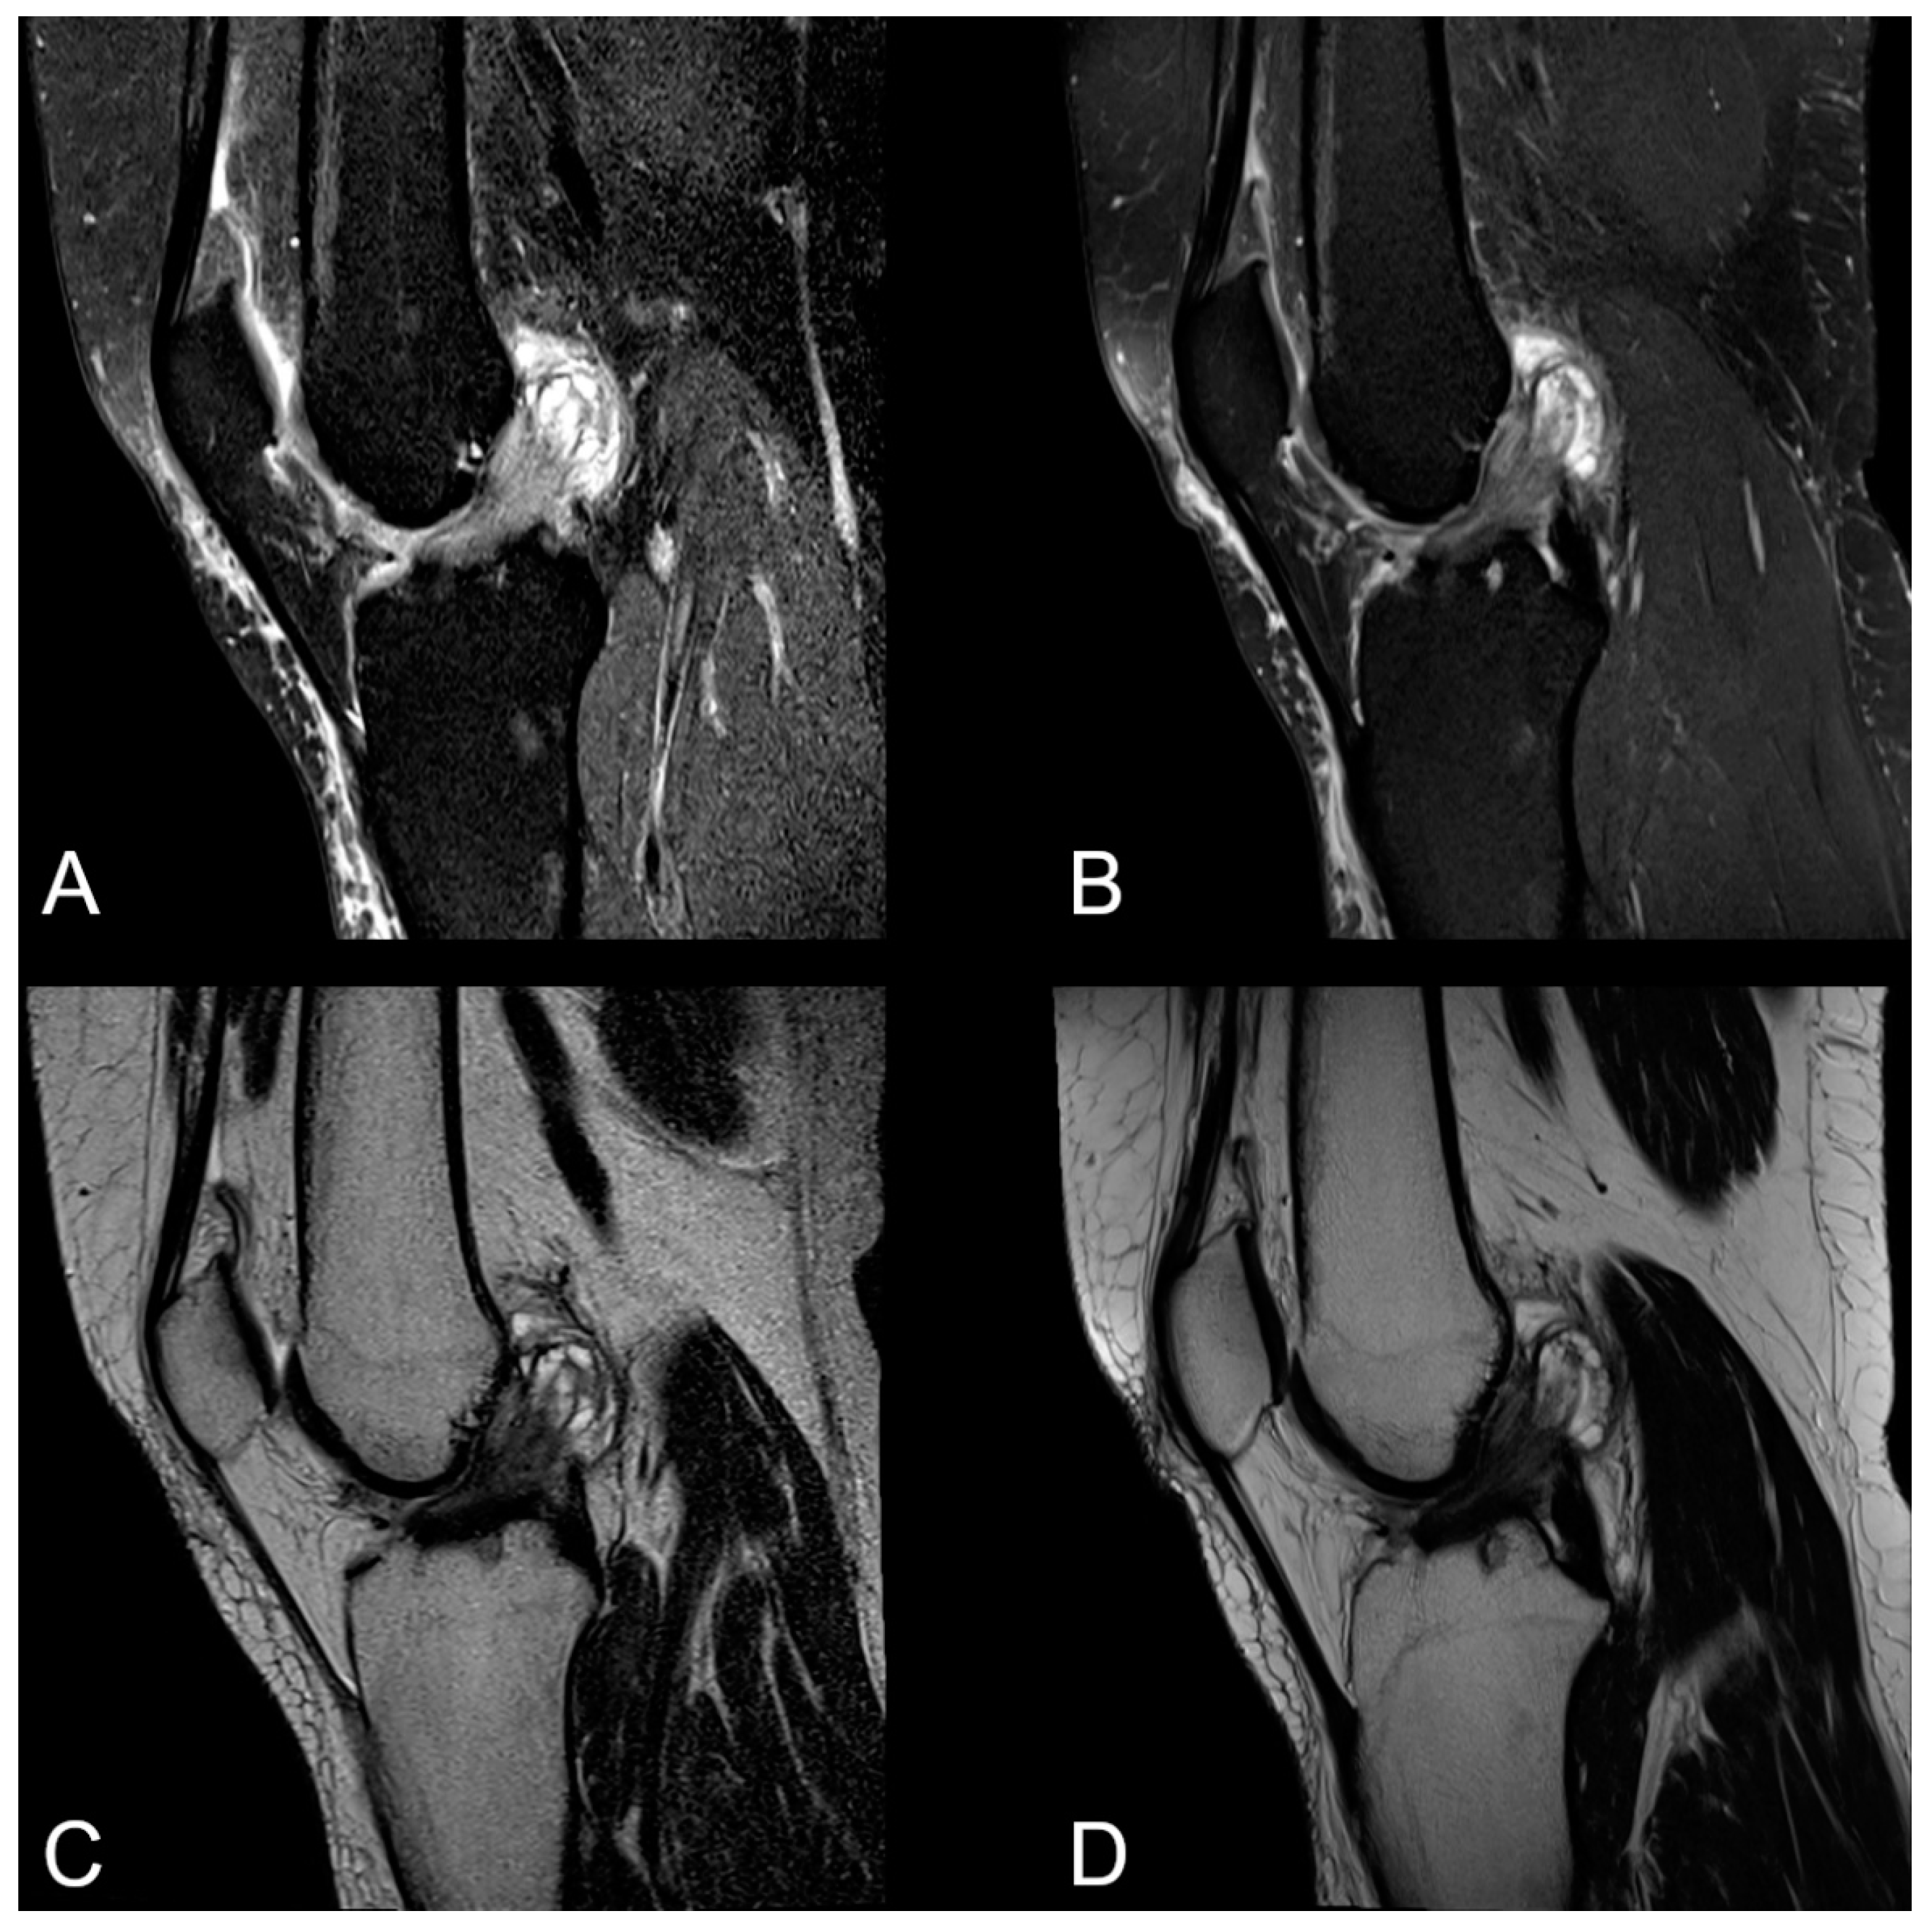

3.2. Visibility of Anatomical Structures and Detected Pathologies